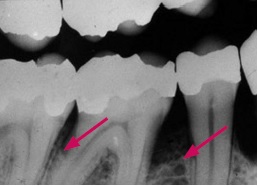

Røntgenbilleder kan vise, hvor fremskreden sygdommen er.

Normalt fæste

Røntgenbilleder af tænder med normalt fæste og tænder med fæstetab. Billederne er taget med fem års mellemrum af den samme patient.

Fæstetab